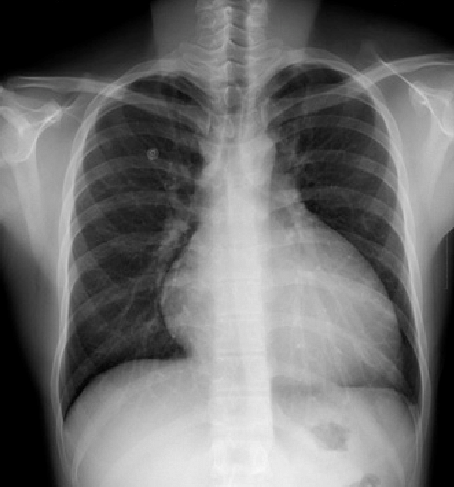

Ученые Института умных систем и искусственного интеллекта НУ представили бесплатную систему диагностирования рентген-снимков грудной клетки. Теперь, любой желающий может воспользоваться этим сервисом на сайте Института.

Система создана на основе технологий глубокого обучения (deep learning), которая позволяет определить тип рентгеновского снимка и визуализировать патологию онлайн, в течение пары секунд. Этот метод позволяет выявлять различные аномалии в грудной клетке. Разработчики уверены, что такой сервис позволит не только помочь врачам в эффективной диагностике патологий, но и снизит затраты на медицинское обслуживание.

Система доступна в виде демо-версии на сайте Института по ссылке: https://issai.nu.edu.kz/xray/. Для того, чтобы воспользоваться системой, врачу необходим сканированный рентген-снимок, который загружается в систему. Диагностика состоит из нескольких этапов: определение изображения («Рентген или Не рентген»), определение типа снимка (грудная клетка, плечо, локоть, голень и тд), и индивидуальная модель глубокого обучения для каждого типа рентгеновского снимка, которая идентифицирует аномалии в каждом изображении.

На данный момент система может определять патологию только грудной клетки, однако в будущем планируется расширить возможности системы до определения патологий других частей тела.